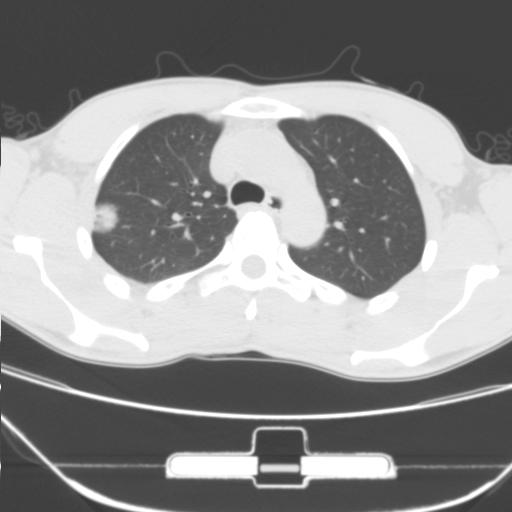

右肺上叶后段近胸膜下结节样异常密度灶,似见分页及毛刺,考虑右肺上叶周围型肺ca,建议穿刺病理检查

缺乏病史,症状体征,但这个孤立结节具备了几乎所有的恶性征象:分叶,毛刺,空泡征,胸膜凹陷征,血管集束。

考虑右肺上叶后段周围型肺癌。